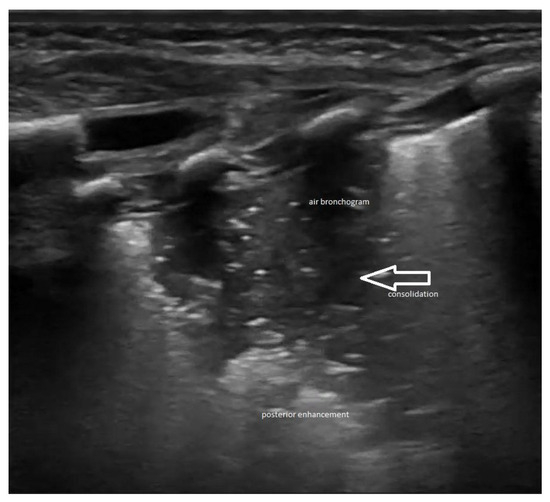

Lung ultrasound

2.3. Lung Ultrasound Criteria/Findings